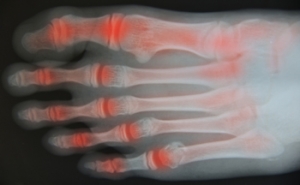

Although rheumatoid arthritis attacks multiple bones and joints throughout the entire body, ninety percent of people who actually develop this condition usually do so in the foot or ankle area. Those who develop this kind of arthritis in the feet usually develop symptoms around the toes and forefeet first, before anywhere else. Rheumatoid arthritis appears to have a genetic component. If it runs in the family, then you will be more likely to develop it as well.

Some of the most common symptoms that are associated with RA include pain and swelling of the feet. Stiffness in the feet is also another common symptom that people experience. Those who have RA in the feet usually feel the pain in the ball or sole of their feet. This can get to be very painful at times. A person's joints can even shift and become deformed after a period of time.

In order to properly diagnose RA in the feet it is usually necessary for a doctor or podiatrist to evaluate the area. Your doctor will also question you about your medical history, occupation, etc., to determine whether anything in your lifestyle may have triggered the condition. There are a number of tests that may be performed to help diagnose RA, such as a rheumatoid factor test. There is, however, no one single test that will tell you for sure if you have RA. There are different X-rays that can be taken as well to determine if a person has RA in their feet.